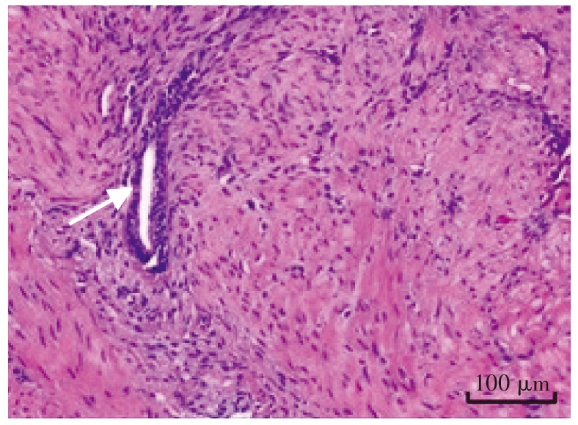

Cystic adenomyosis is a rare type of adenomyosis. Its clinical manifestations are characterized by progressive dysmenorrhea and menstrual abnormalities, accompanied by chronic pelvic pain, dyspareunia and decreased fertility. A case of cystic adenomyosis was reported. The patient was admitted for intermittent lower abdominal pain for more than 3 months. The pelvic MRI combined with carbohydrate antigen 125 (CA125) test suggested the diagnosis of uterine myometrium endometriosis cyst and underwent hysteroscopic resection of endometriosis lesions. Chocolate-like effusion was seen during the operation. With these findings and postoperative pathological results, the patient was diagnosed with cystic adenomyosis. The patient received four cycles of gonadotropin-releasing hormone agonist postoperatively. After 5 months of follow-up, the clinical symptoms were completely relieved and there was no recurrence. The clinical manifestations of cystic adenomyosis have significant heterogeneity. Ultrasound, MRI and CA125 are important auxiliary methods for the diagnosis of this disease. Surgical resection of the lesion is the main means of treatment. Postoperative adjuvant hormone therapy can consolidate the surgical effect, reduce the risk of recurrence and improve the prognosis of fertility.